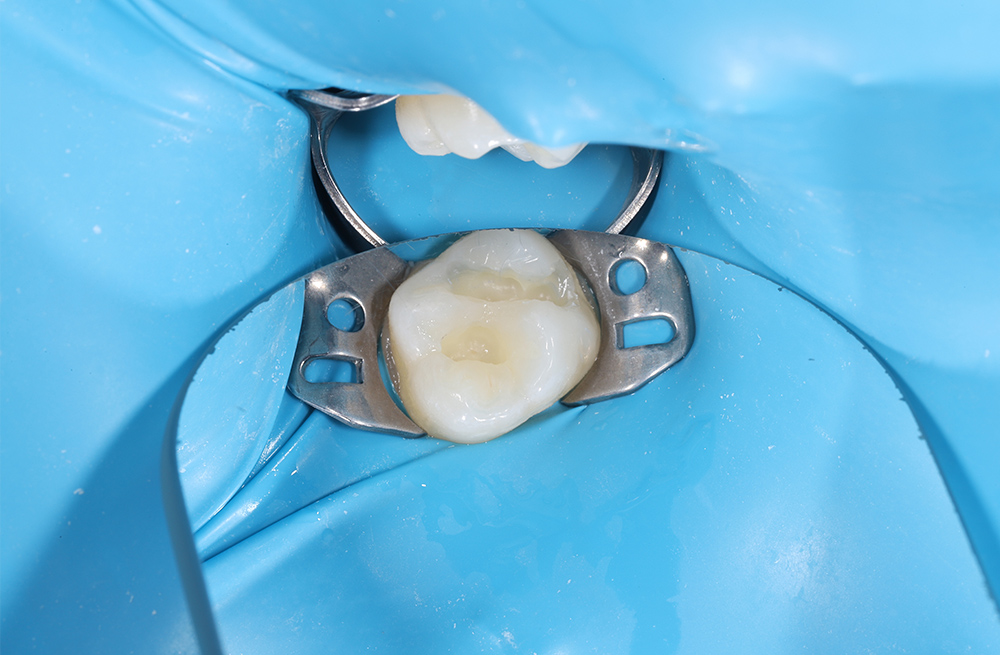

Лечение кариеса на жевательной поверхности постоянного зуба у подростка